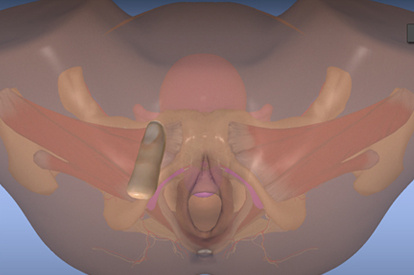

As a strong didactic tool, the PELVIC Mentor provides trainees with immediate feedback on anatomical recognition and the opportunity to practice pelvic exams accurately. The unique combination of the model’s anatomical structure, finger sensation and virtual model provide the most effective training tool to date, aimed at developing the physician’s confidence during pelvic examinations.

The self-study training module has led to substantial improvements in internal rating with a proportion of structures recognized from 31.25 to 87.5 %. The preliminary results suggest that the 3D virtual simulator enhances and facilitates learning the anatomy of the pelvic floor.